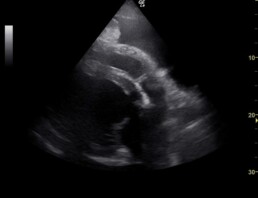

Ebenso lag ein hochgradiger Pleuraerguss vor.

Abb. 3: Herzsilhouette mit Pleuraerguss